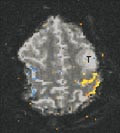

Ved økt hjerneaktivitet (f.eks. pga. motorisk aktivitet, sensoriske stimuli eller tankevirksomhet) vil hjernecellenes oksygenforbruk øke. Dette gir en reflektorisk økt blodgjennomstrømning til det aktuelle området av hjernen. Den økte blodstrømmen overkompenserer for det økte oksygenforbruket, slik at veneblodet som drenerer de aktive områdene, inneholder mindre deoksyhemoglobin enn hva tilfellet er uten aktivitet. Mindre deoksyhemoglobin fører til økt MR-signal sammenliknet med hviletilstanden (13). Økningen i signal er for liten til å oppdages direkte visuelt, men ved å gjøre forsøk med avvekslende aktivitet og ingen aktivitet kan man ved hjelp av statistiske metoder oppdage og fargekode de områdene som veksler i signalintensitet i takt med forsøket. Metoden kalles gjerne på engelsk ”functional MRI” (fMRI), og er en teknikk som hovedsakelig har vært benyttet til forskningsformål. En svært nyttig praktisk anvendelse er utredning før hjernekirurgi for å kartlegge om viktige hjerneområder (f.eks. den motoriske bark) vil affiseres av inngrepet (fig 5) (14, 15).